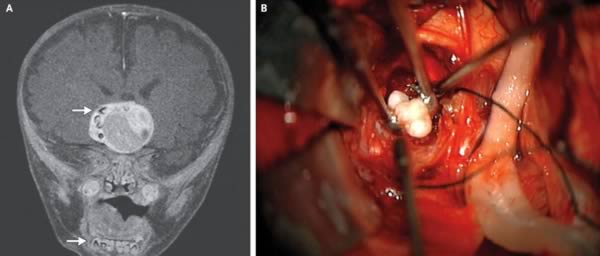

4. Редкая опухоль в мозгу младенца оказалась зубом

4-х месячный ребёнок из штата Мэриленд может оказаться первым человеком, который имел в мозгу опухоль, оказавшуюся зубом. Впервые врачи заподозрили, что-то не так, когда голова ребёнка, казалось, начала расти быстрее, чем это свойственно детям его возраста. Сканирование мозга выявило опухоль, которая содержала в себе структуры, очень напоминающие человеческие зубы, обычно находящиеся в нижней челюсти. Опухоль была удалена, и сейчас мальчик чувствует себя хорошо.